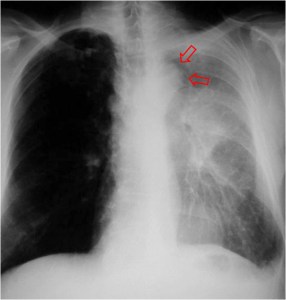

SIGNO DE LA ALTERACIÓN DEL CONTORNO AÓRTICO

La irregularidad, abombamiento o borramiento del arco aórtico en la radiografía de tórax en bipedestación o en decúbito supino, en un paciente con traumatismo torácico, obliga a descartar rotura aórtica como causa de dicha alteración. La flecha muestra el contorno aórtico anómalo. Además, hay un aumento de densidad en el hemitórax izquierdo correspondiente a derrame pleural –hemotórax en este caso-, que refuerza la sospecha de rotura aórtica.